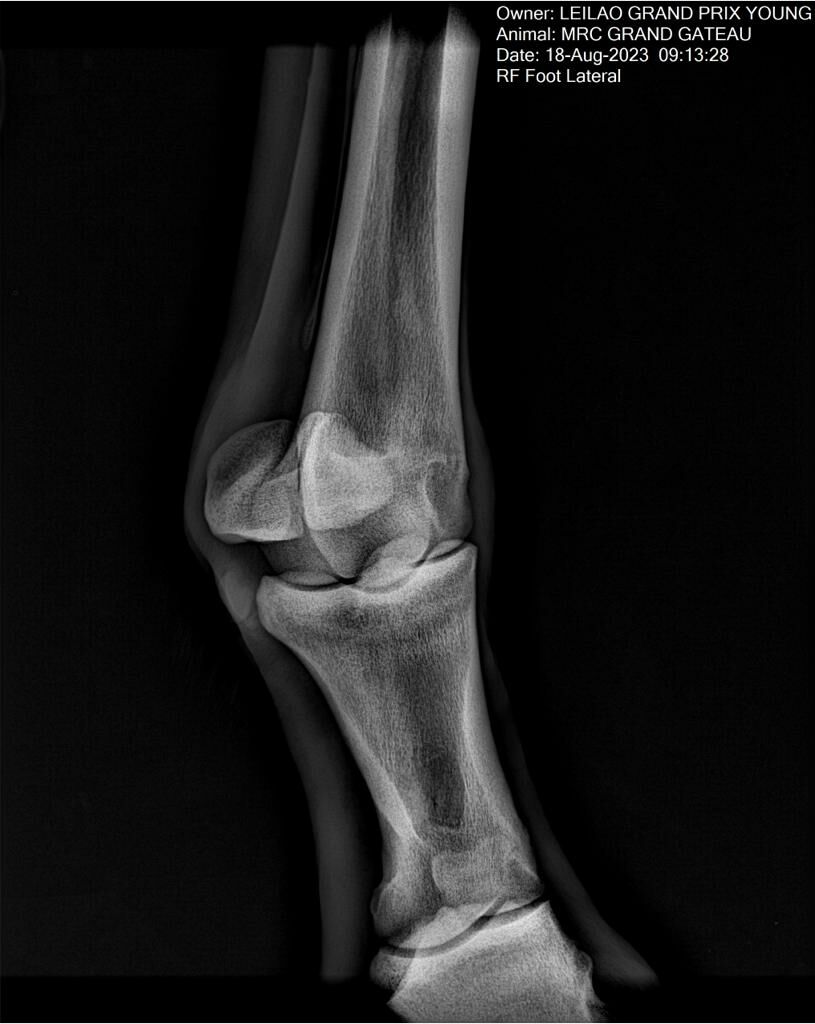

MRC GRAND GATEAU

:: RAIOS-X DO LOTE